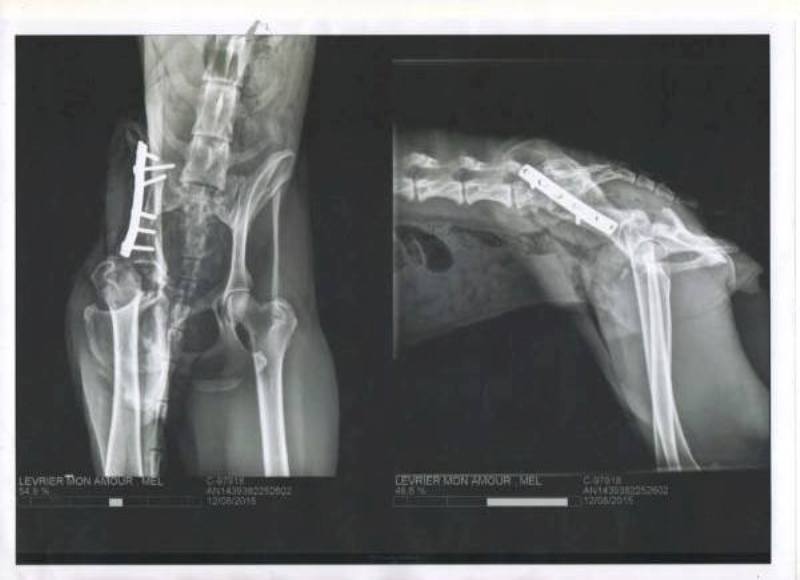

Mel a été opérée de son bassin et de son fémur, l'opération est une réussite,

elle apprend à poser sa patte maintenant.

"Coucou, c’est moi MEL,

je vous avais promis de vous donner de mes nouvelles ; avec mes mots,

je vous dis juste OUF, et voilà, c’est fait…….. J’ai une patte toute neuve, même que

dedans, il m’a mis un bijou !! une plaque comme ils disent avec des vis…

L’intervention sur le bassin de Mel a été une réussite, le chirurgien a atteint ses objectifs :

redresser le bassin, réaligner les abouts osseux fracturés puis stabiliser au moyen d’une

plaque avec vis qu’elle gardera à vie si elle le supporte bien.

Une radiographie de contrôle aura lieu dans 7-8 semaines ; durant ce temps, pas de course,

pas de saut et des sorties en laisse puis sera mis en place un programme de physiothérapie ;

Regardez sur les photos jointes, son bassin avant et après….

AVANT

APRES